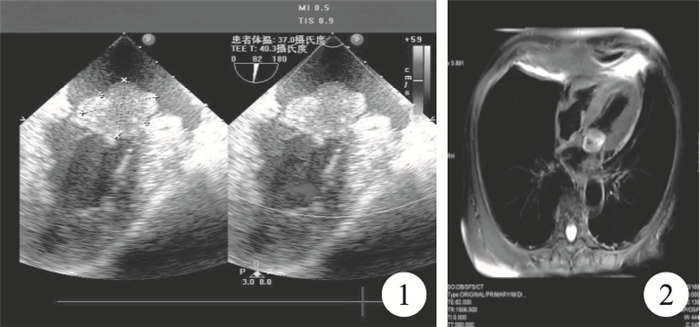

臨床資料??患者,男,63歲,活動后疲乏、氣促20余d入院。入院查體:體溫36.4℃,脈搏84次/分,呼吸18次/分,血壓128/92 mm Hg。神志清楚,心律齊,心尖區聞及雙期雜音。心電圖示竇性心律,左心室高電壓。術前經食管超聲心動圖(TEE)檢查示左心房內異常團塊回聲大小約2.0 cm×3.0 cm×1.5 cm,稍弱回聲,附著于二尖瓣前葉根部,基底較寬,團塊部分與二尖瓣前葉粘連,舒張期部分團塊隨心臟運動進入二尖瓣口(圖 1)。心臟磁共振成像(MRI)示:左心房內見等T1稍長T2信號腫塊影,大小約3.1 cm×2.6 cm×1.8 cm,邊界較清楚,腫塊基底部附著于二尖瓣,心臟電影序列見腫塊經二尖瓣口進入左心室(圖 2)。